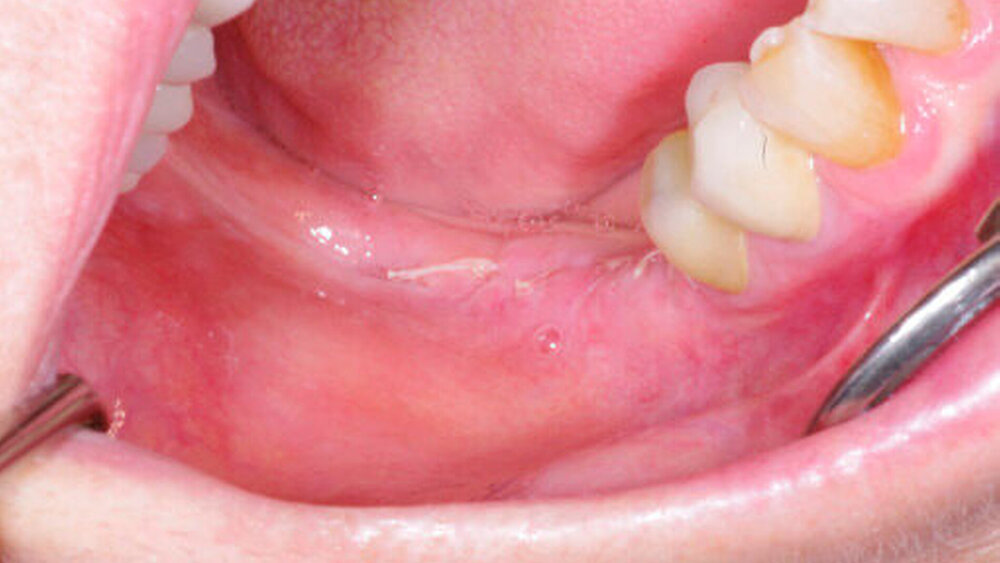

Die innovative Kombination aus weißem Faden und schwarzer Nadel ermöglicht exzellente Sichtbarkeit im OP-Gebiet. DirectFlon ist ein monofiles Nahtmaterial. Die glatte Oberfläche verhindert die Akkumulation von Bakterien und Essensresten. Im Gegensatz zu anderen Nahtmaterialien verhindern die Enden des PTFE-Fadens Irritationen an den Schleimhäuten.

Last but not least: Aufgrund seiner geringen Kapillarwirkung kann der Faden außerdem einfach entfernt werden. Das beeinflusst die Wundheilung positiv und verringert die Schwellung für den Patienten.